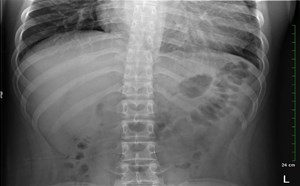

2021 1st Place Emage Winner: Abdominal Distention: Prepare for the Worst